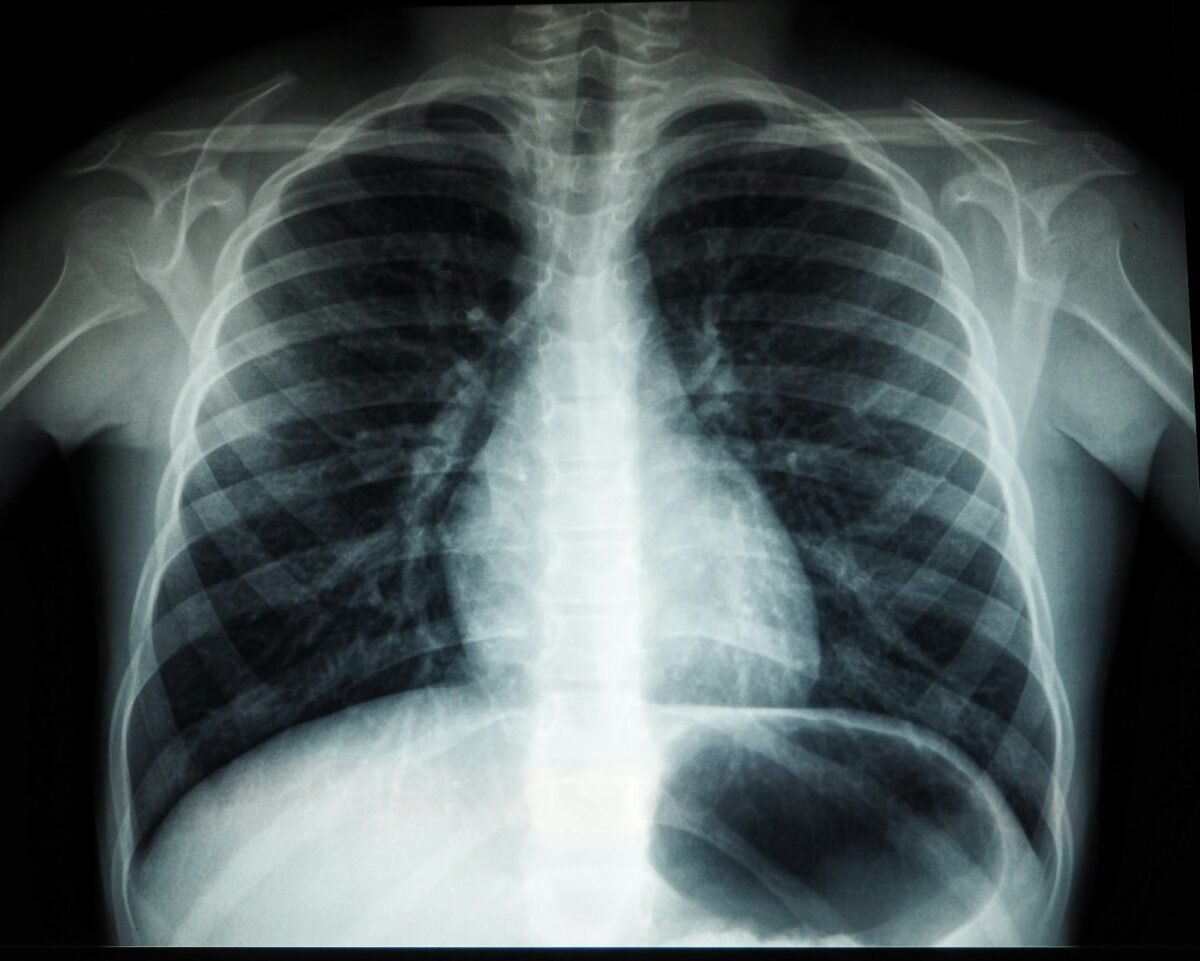

Día Mundial de la Radiología

El Día Mundial de la Radiología (también llamado International Day of Radiology) se celebra de manera anual desde el año 2012 cada 8 de noviembre y tiene como objetivo principal dar visibilidad al papel de la imagen médica —radiografías, tomografía, resonancia, ecografía, medicina nuclear, radiología intervencionista— en el diagnóstico, tratamiento y seguimiento de enfermedades. La … Leer más